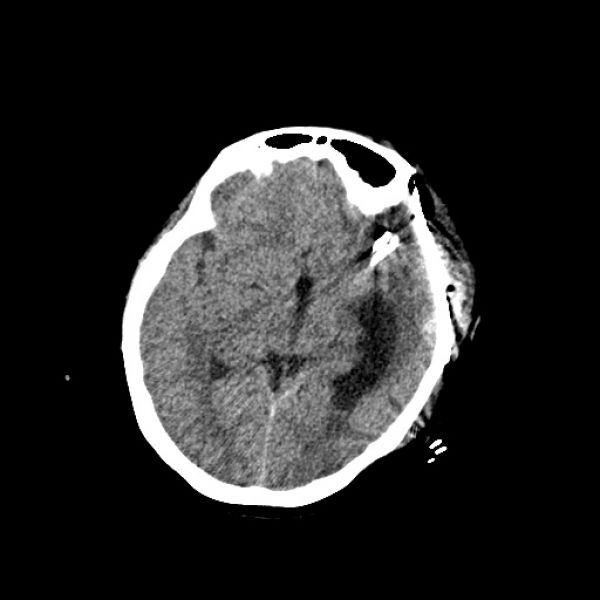

病区主任朱英杰高度重视,认为患者此次主要以头痛不适住院,结合既往病史,考虑头痛与颅内动脉瘤仍有一定的关系,与家属仔细商议病情后,建议复查全脑血管造影。由田志副主任完成了选择性全脑血管造影术,术中发现左侧大脑中动脉M1段分叉部可见一动脉瘤夹影,M1段分叉部可见一囊状动脉瘤,右侧颈内动脉眼动脉段可见一小动脉瘤。患者颅内多发动脉瘤!且是短时间内的复发,若动脉瘤一旦“爆炸”,病情会急剧恶化,患者愈后则极差。

经过与患者家属的详细沟通和精心准备后,由朱英杰病区主任主刀、田志副主任医师一助,有条不紊的在显微镜下分离血管,小心保护神经组织,最终历时4小时,完成左侧大脑中动脉M1段分叉部动夹闭+包裹术,术后在神经外科二病区及ICU医师的共同精心治疗下,患者逐步恢复好转,得益于良好的神经显微技术,患者未出现新发的神经功能缺失,3周后步行出院。